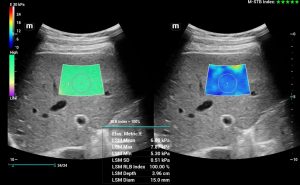

STE - Sound Touch Elastografia, 2D shear wave elastografia v reálnom čase

HiFR STE (Shear wave elastografia🙂 ZST+ UZV platforma umožňuje 10 krát rýchlejší STE frame rate ako u štandardných UZV prístrojov pri zachovaní hladkosti a konzistentnosti obrazu. Senzitívnejšia detekcia pohybu, lepšia stabilita vyššia presnosť. Unikátny M-STB index indikujúci pohybovú stabilitu obrazu. Presná kvantifikácia tuhosti pečene pomáhajúca pri gradingu a prognóze fibrózy a cirhózy pečene

STE - Sound Touch Elastografia, 2D shear wave elastografia v reálnom čase